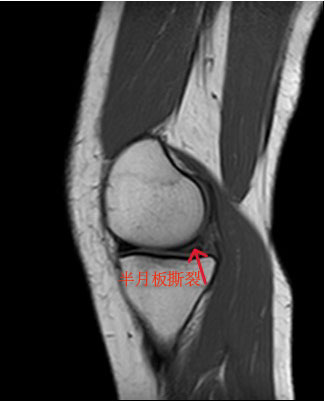

李女士,37岁,右膝关节疼痛伴活动受限3月,伴有跛行,上下楼梯疼痛,有蹲起困难,有卡感和交锁,门诊核磁检查提示:半月板撕裂。门诊以“右膝半月板撕裂”收入院。完善术前检查,明确无手术禁忌症后,应用缝合器技术将撕裂半月板缝回它原本的位置。

术前右膝关节冠状位核磁可见半月板在多个层面上出现高信号(红色箭头所指位置)